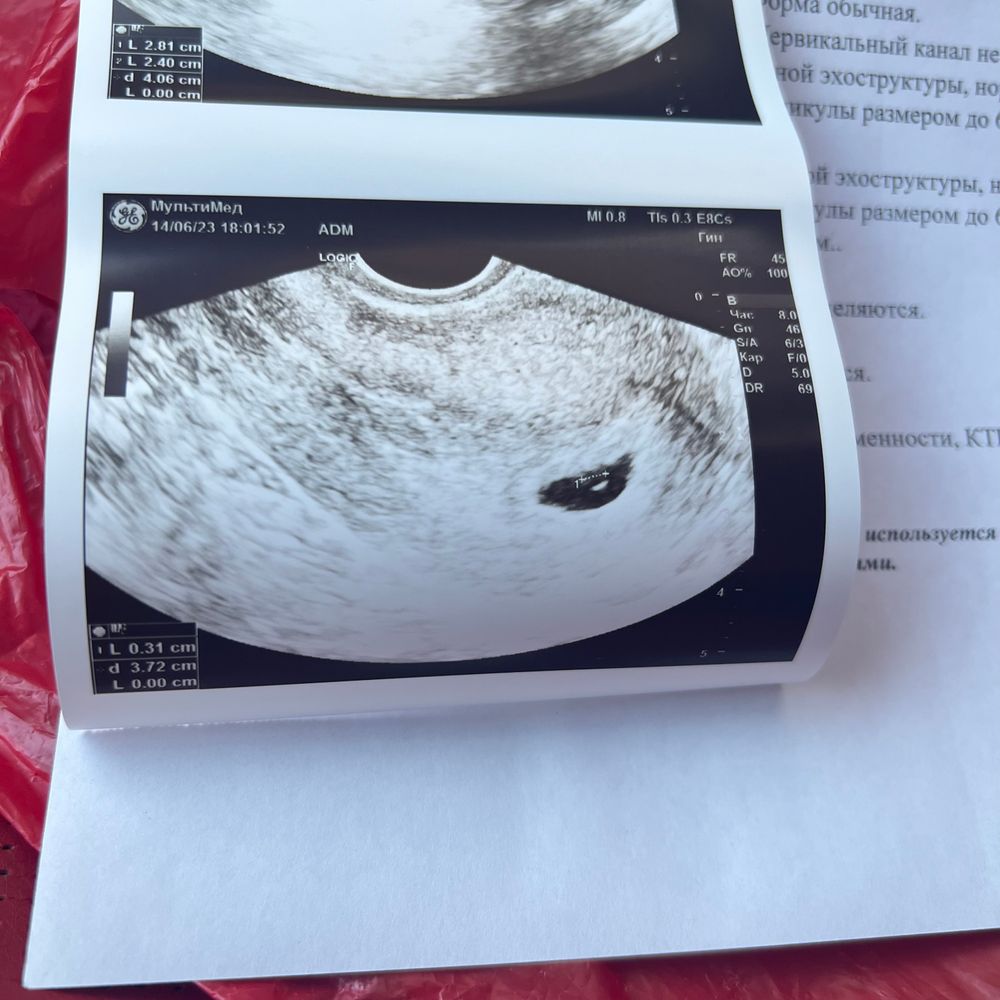

Узи 5 недель

Подскажите пожалуйста, а когда увидели эмбрион? У меня на сроке 5 недель и 4 дня было только плодное яйцо с подросшим желточным мешочком. Что-то сегодня начала переживать😬

Tatiana, у меня тоже в 5,1 по месячным пя было 3,6 мм, овуляция была на 18 дц.